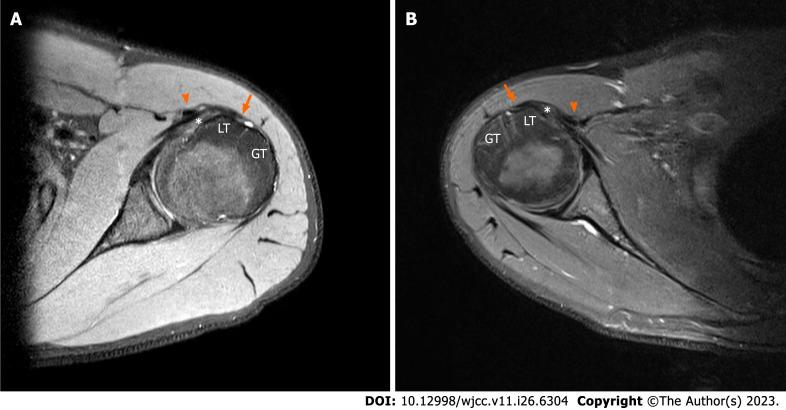

A 23-year-old male presented to our outpatient clinic with left side dominant pain in both shoulders. The patient had no history of trauma or overuse. The patient underwent intra-articular injection and physical therapy, but his symptoms aggravated. Based on preoperative imaging, the diagnosis was bilateral dislocation of the LHBT. Dysplasia of the bicipital groove was detected in both shoulders. Active dislocation of the biceps tendon over an intact subscapularis tendon was identified by diagnostic arthroscopy. Staged biceps tenodesis was performed and continuous passive motion therapy was administered immediately after surgery. The patient's pain was resolved, and full functional recovery was achieved, and he was satisfied with the condition of his shoulders.

一名23岁男性因双肩左侧为主的疼痛前来我院门诊就诊。患者无外伤或过度使用史。患者接受了关节内注射和物理治疗,但其症状加重。根据术前影像学检查,诊断为双侧肱二头肌长头肌腱脱位。双侧均检测到肱二头肌沟发育异常。通过诊断性关节镜检查发现肱二头肌肌腱在完整的肩胛下肌腱上主动脱位。分期进行了肱二头肌肌腱固定术,并在术后立即给予持续被动运动治疗。患者疼痛缓解,功能完全恢复,对肩部状况满意。